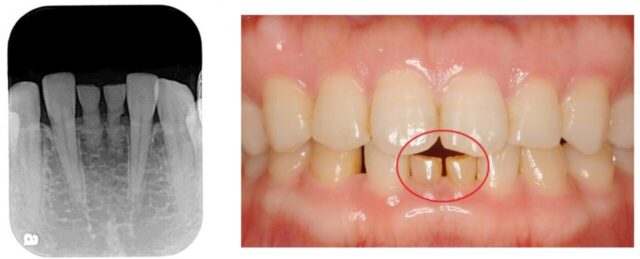

肉眼では問題がないように見えても、歯茎の中で犬歯が隣の歯の根にあたっています。

レントゲン検査で、このような問題を早期に発見できます。